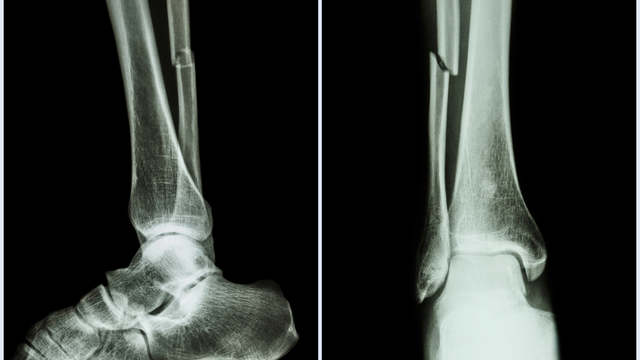

Gãy xương